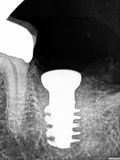

fredlibc | all galleries >> Galleries >> NSankhyan - immediate 37 > R1.jpg

R1.jpg